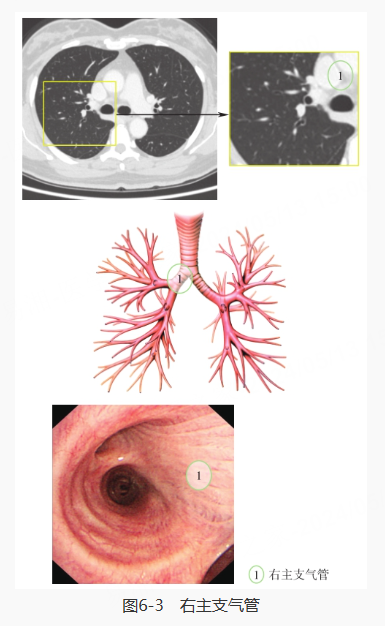

继续探入,先对右肺进行探查,分别是右主支气管、右肺上叶·中间段支气管、右肺上叶、右肺中叶·下叶、右肺中叶、右肺下叶背段和右肺下叶基底段: